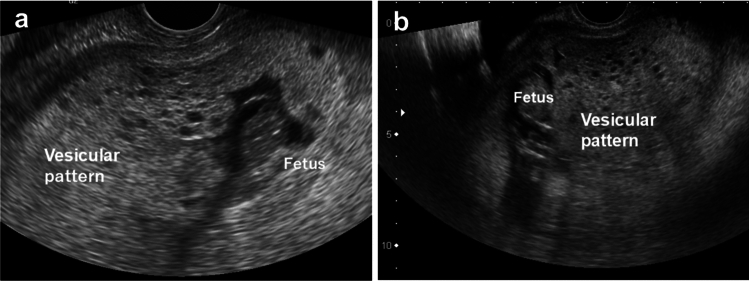

Methods:  We reviewed medical records of patients with CHMCF treated at our hospital from 2000 to 2020 and summarized clinical data, including maternal age, pregnancy details, delivery outcomes, fertility treatments, serum human chorionic gonadotropin (hCG) levels, and ultrasonography findings.